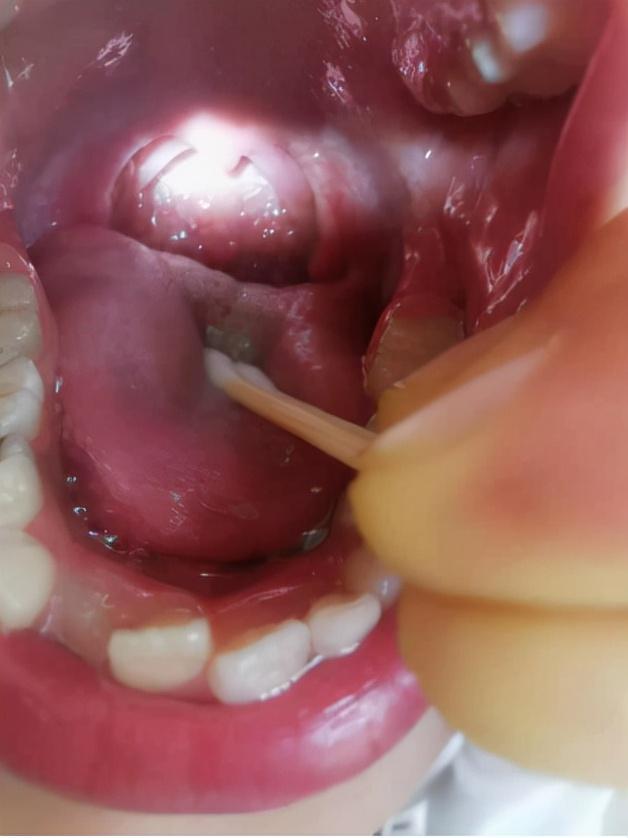

图7-肠道功能检测2021年5月

2021年5月复诊时,小患者的肠道功能里还有很轻微的麸质过敏、肠道炎症、葡萄糖醛酸酶超标和胰弹性蛋白酶不足。但是肠漏指标(解连蛋白)已经恢复到了正常水平。

这个小病人的肠漏相当严重(图6),如果不及时治疗,就会形成恶性循环。另外需要注意的是,在修复肠漏的同时,控制饮食、调节情绪是非常重要的,这主要和家庭环境有关,否则肠漏很容易反复。

图6-肠漏检测2020年10月